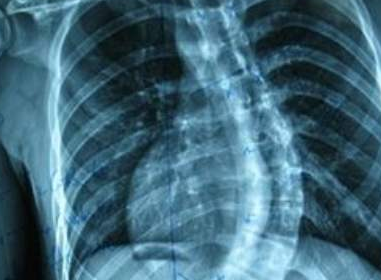

做什么检查确诊强直性脊柱炎?(河南治疗强直性脊柱

河南治疗强直性脊柱炎医院介绍到如果想要确诊强直性脊柱炎,主要是通过病人的临床症状以及…[详情]

强直性脊柱炎

AS ①晚期 ②重度 病史:5年+

治疗后骶髂关节疼痛消失,腰椎前屈、背伸侧弯活动自如,膝关节无压痛感,复查血沉、C反应蛋白、等各项检查均已达到临床康复的标准。